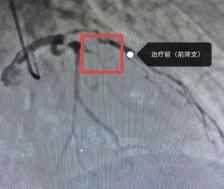

近期,六安市中医院心内科因心梗入院的患者接连不断,12月19日一天就收治了5名急性心肌梗死的患者因病情危重,其4名均急诊冠脉介入干预治疗。急性心梗如此凶险,而且冬天又是心梗高发的季节,我们应该如何预防呢?